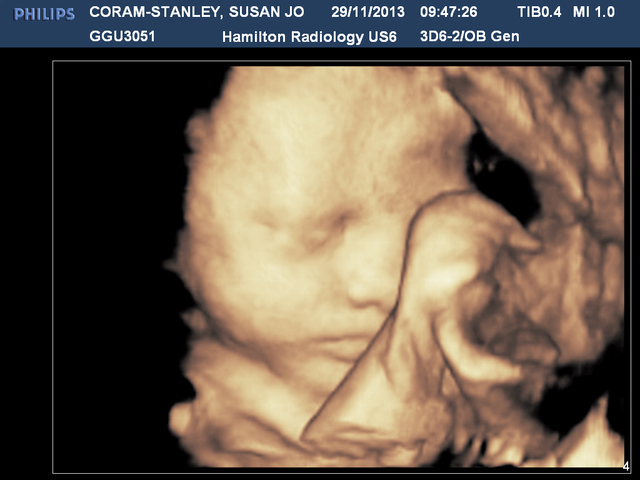

At 32 weeks we got a 3D scan. We combined this with our dating scan so were in there for AGES. But the scan was amazing, was so incredible seeing baby move about in there, in 3D. He waved and waggled his fingers, did a huge laugh - or cry or something, and just seeing him was truly incredible.